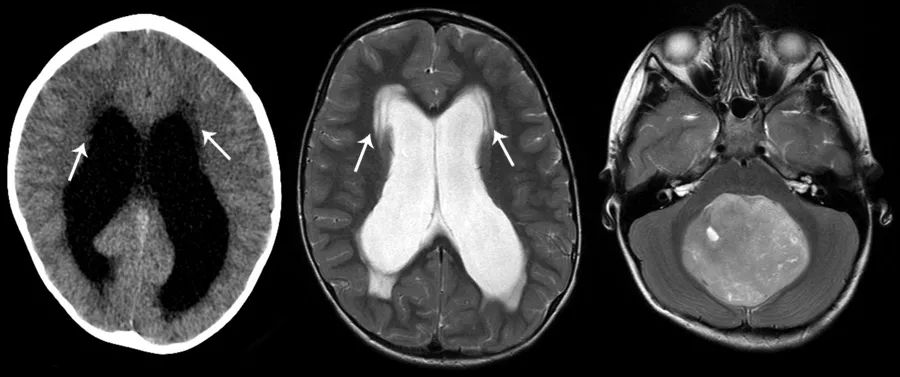

间质性脑水肿是一种由于脑室内压力增加而引起的脑水肿,由于脑脊液通过室管膜转移到脑室周围的脑实质中而引起,常见于急性阻塞性脑积水患者的侧脑室周围。掌握间质性脑水肿的特点,并与额叶前方信号的正常轻度增加,以及枕叶后方脑室炎相鉴别是很重要的。

CT上,侧脑室周围可见脑室周围条片状低密度影,相邻脑沟消失,以及阻塞性脑积水的其他特征。MRI上的FLAIR序列对这种脑水肿的检测尤为敏感,侧脑室周围可见T2/FLAIR高信号的晕圈,边界通常较清。

图5 侧脑室周围可见条片状异常密度,CT上呈低密度,MRI的T2WI上呈高信号,边界较清(左、中)。本例患者的阻塞性脑积水由后颅窝占位导致(右)。